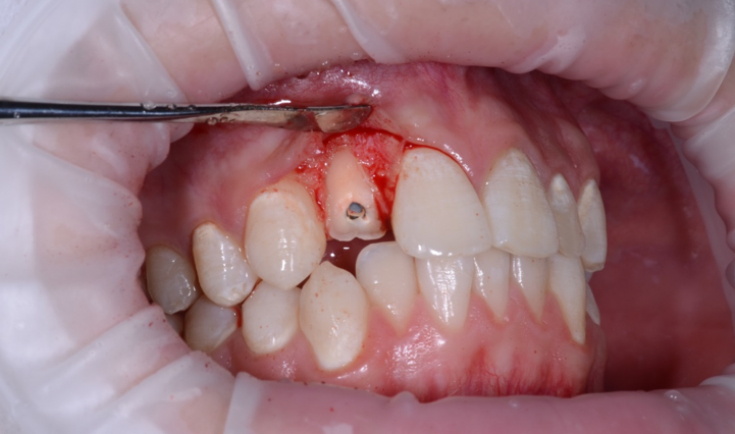

In case of a minor fracture, a filling is placed. For more severe damage, orthodontic treatment and a crown will be required. When the root is injured, it is removed, and an implant is placed in its place. Complications are periodontitis, stomatitis, pulpitis.In case of dental injuries of varying degrees, it is recommended to seek help from a dentist as soon as possible. Depending on the severity of the damage, you will be prescribed treatment and oral care. Prevention of dental injuries consists in the correct and safe lifestyle of a person. All safety equipment must be worn when working in hazardous work environments. Athletes are advised to wear mouthguards and a safety helmet every time.